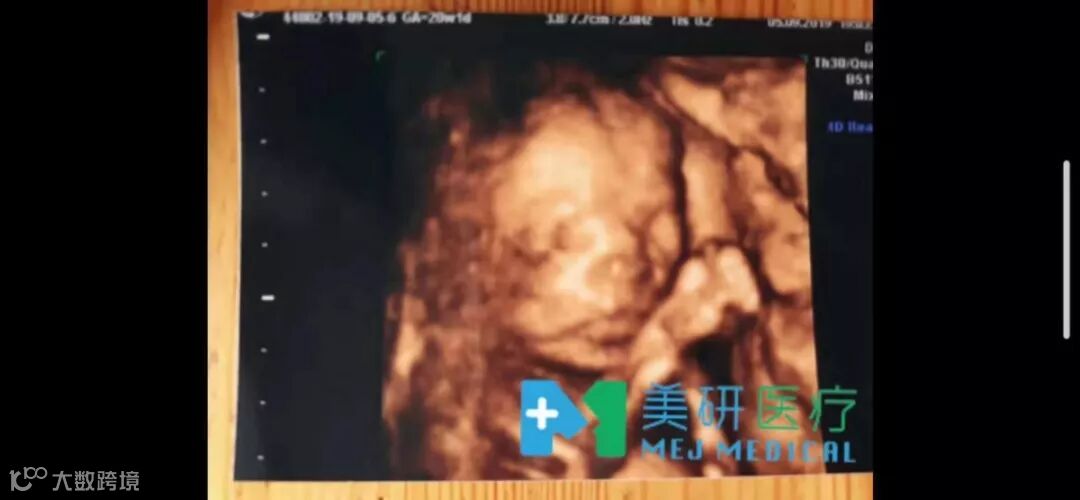

今年大热的俄罗斯助孕

一个孕妈,已经20周了,宝宝一切健康。

一个孕妈,32周了,产检完妥妥的。

加油小宝贝们!

俄罗斯AVA医院的孕母真的都非常棒,我们至今都还没发生过流产的情况,期待更多好孕!更多新生!